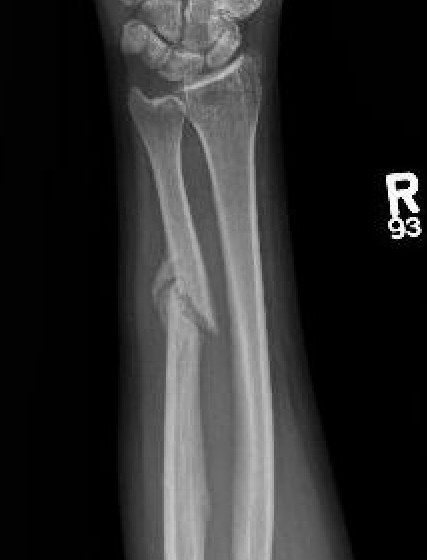

- 21 cases of nonunion of isolated ulna fractures

- associated with > 50% displacement

Increased nonunion rates with midshaft versus distal fractures

- increased nonunion with midshaft (30%) versus distal 1/3 fractures (2%)

Ulna nonunion after plating